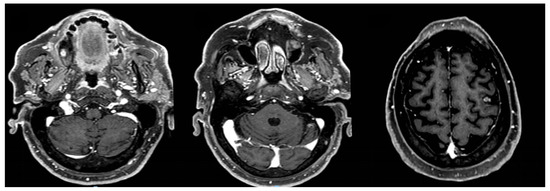

2. Case Report